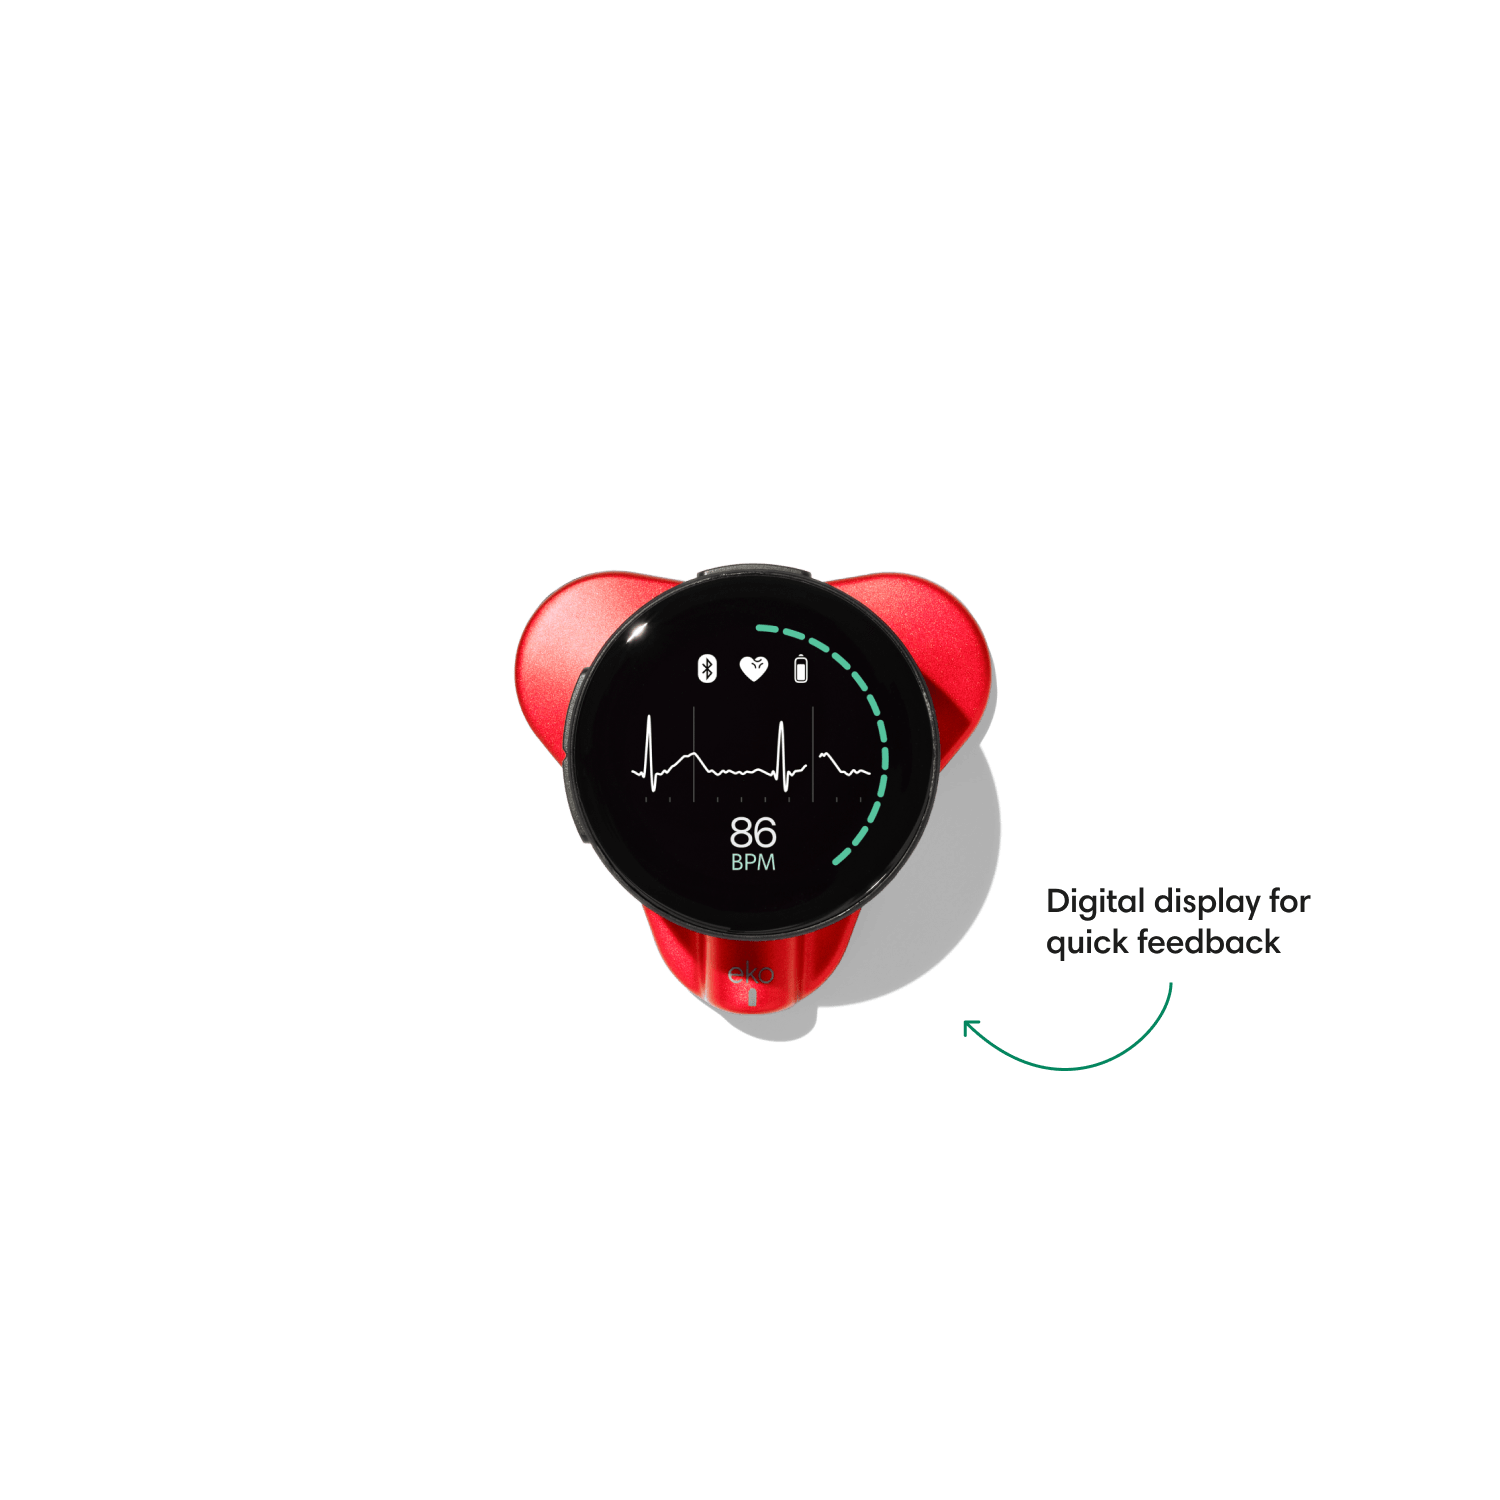

Go beyond sound alone.

For the first time ever, measure heart rate, visualize 3-lead ECG, and see detection results — right on a built-in, full-color display.